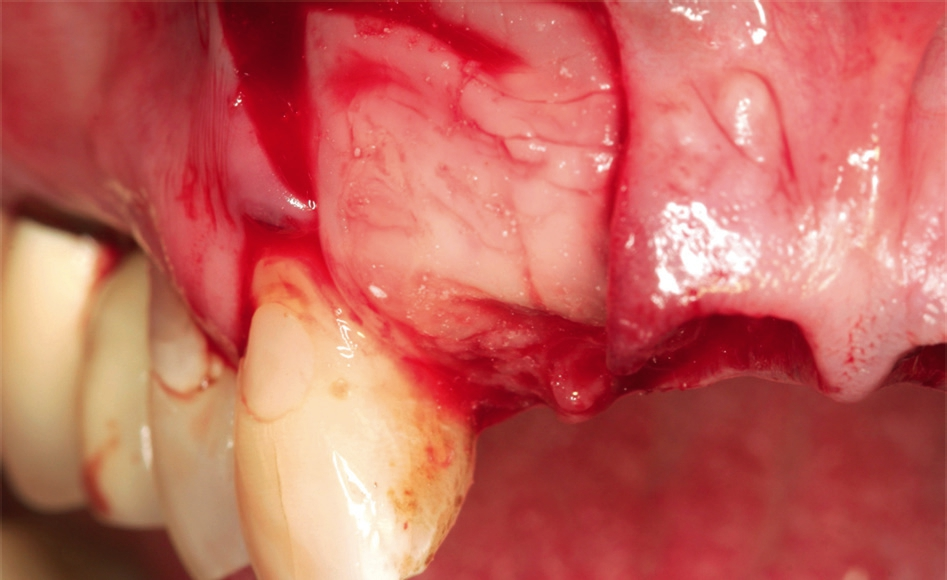

Anschließend wurde das Implantatbett durch den Ring vorbereitet und ein Straumann Bone Level Tapered (BLT) Implantat ø 3,3 mm gesetzt (Abb. 7 und 8). Insgesamt erfolgte die Implantation von zwei maxgraft® bonerings 6 mm und zwei Straumann BLT Implantat ø 3,3 mm 10 mm (Abb. 9). Zur Unterstützung der Weichgewebeheilung wurde platelet-rich fibrin (PRF) aus dem Blut der Patientin gewonnen (Abb. 10). Das PRF wurde sowohl in Verbindung mit dem Knochenersatzmaterial (cerabone®) (Abb. 11), als auch als Membran über der Barrieremembran (Jason® membrane) (Abb. 12) eingesetzt. Zum Erhalt der 1er Schneidezähne wurde eine Socket Preservation mit einem Knochen-Schleimhaut-Transplantat aus der tuber maxillae durchgeführt (Abb. 14 und 15). Explantation erfolgte mithilfe eines 6er Trepans rechts und links aus dem Kieferkamm (Abb. 14).